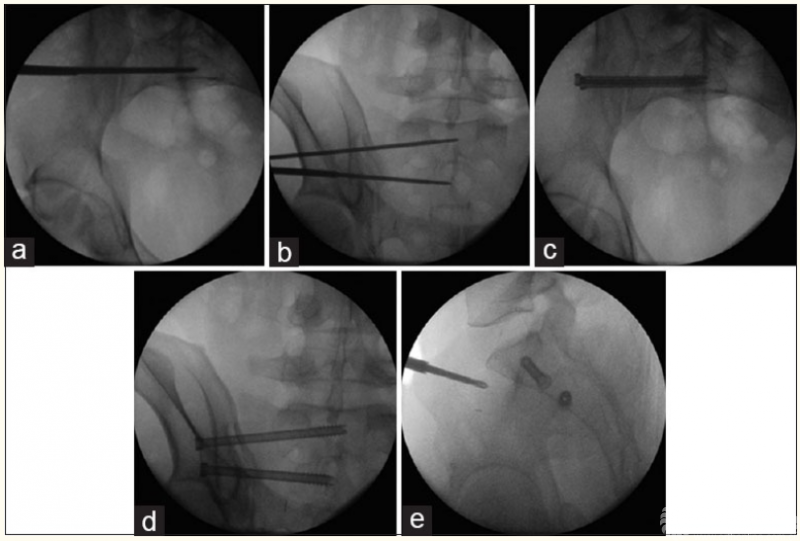

2、骨盆髋臼骨折的机器人辅助手术

3、股骨颈骨折的机器人辅助手术